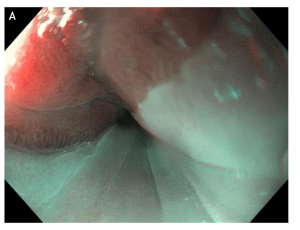

Figure 2 Double mirror flat inlet patches in (A) white light endoscopy vs (B) optical chromoendoscopy (narrow band imaging), in a middle age woman with Helicobacter pylori-associated gastritis and globus sensation ameliorated after the eradication therapy.